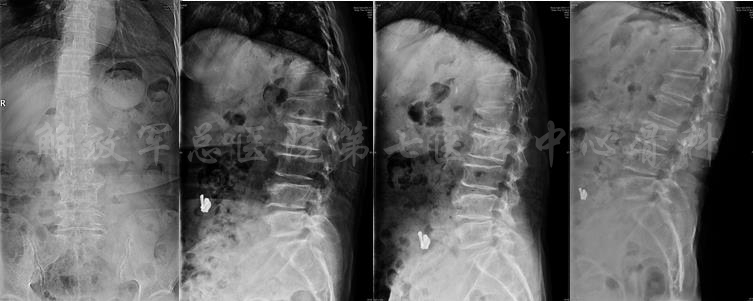

影像学检查

X线片

X线全长片:胸腰段Cobb角(L2-T11):25度;腰椎生理前凸:PI:53、PT:38、SS:15、LL:20;膝关节的屈曲畸形5度

MRI